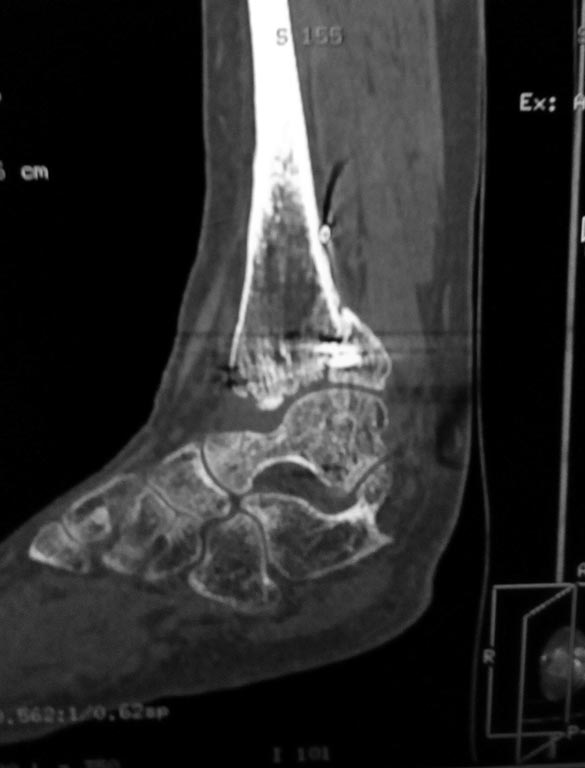

Мужчина, 1987 г.р. получил травму 10.2014. ДТП. Закрытый двухлодыжечный

перелом костей костей левой голени, перелом заднего края большеберцовой

кости с подвывихом стопы кзади, кнаружи. Наложен дистрактор.

Операция 10.2014: закрытая репозиция, остеосинтез спицами,

винтами. В дальнейшем произошло ожидаемое усугубление нарушений

взаимоотношений в голеностопном суставе.